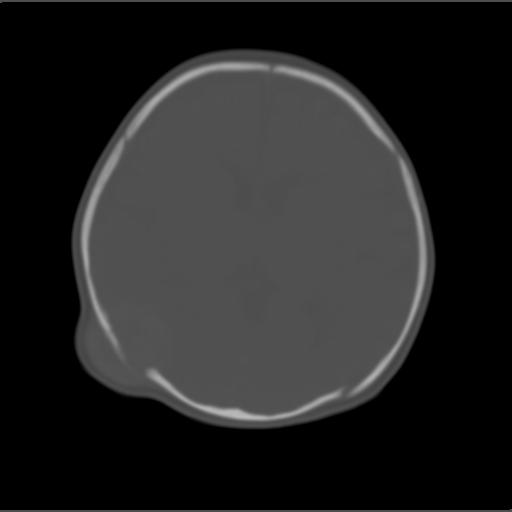

f2m出生已来可见右侧枕部见包块,质地软,无外伤史。包块处ct值16-67hu,大小约3.1x3.2cm左右。

局部颅骨破坏,并以破坏为中心的高密度肿块影,内示软骨影,考虑颅骨软骨瘤.

仔细看颅骨是分离

骨质还算完整。

有无产伤?血肿机化.(颅盖骨是膜化骨,不存在软骨瘤)